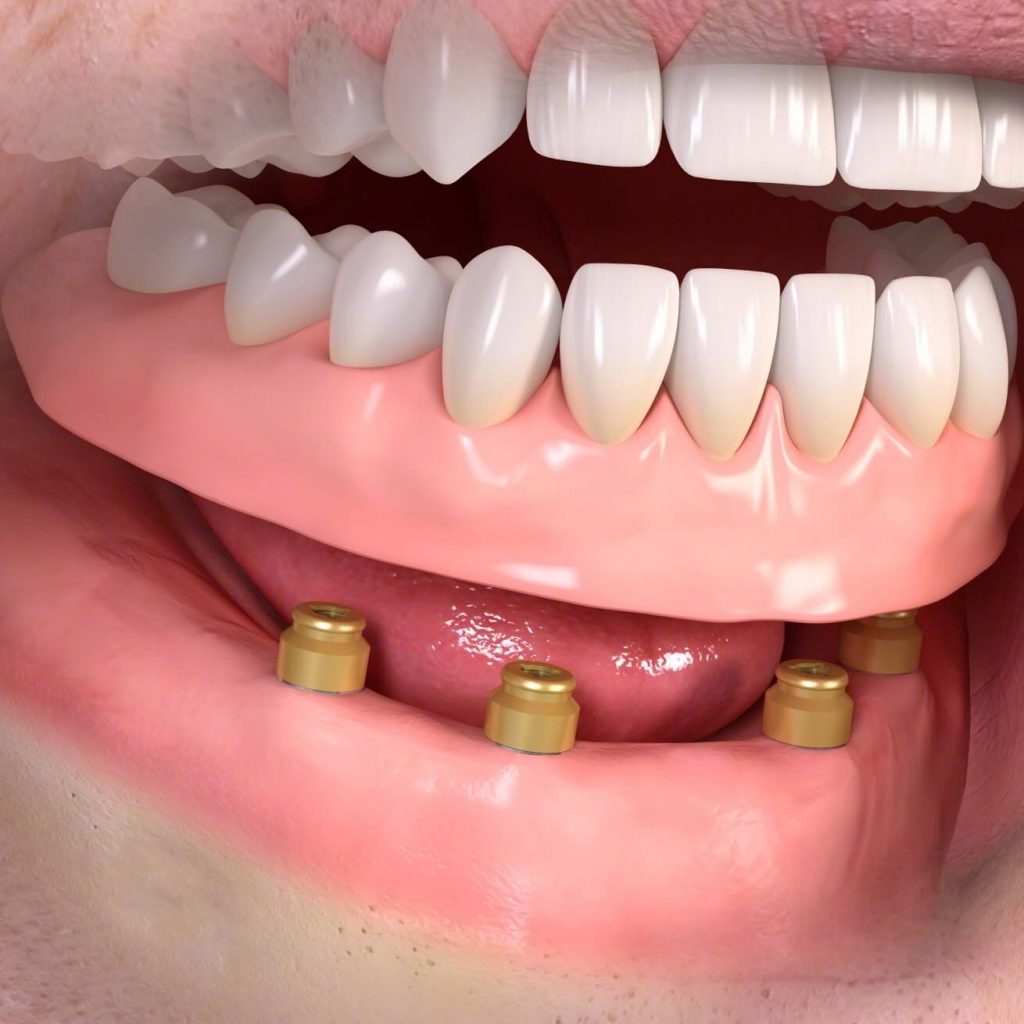

Implantátumokkal rögzített műfogsor

Az implantátumok segítségével rögzített kivehető fogsor minden szempontból előnyösebb a hagyományosan rögzített műfogsor fajtáknál. Teljes foghiány esetén ez fokozottan igaz. Könnyű ki- és behelyezni, és nagyságrendekkel jobb rágóstabilitást biztosít, ezáltal lényegesen javítja viselője komfortérzetét, magabiztosságát és életminőségét. Már 2-4 fogimplantátum beültetésével is tökéletes rögzítés érhető el.